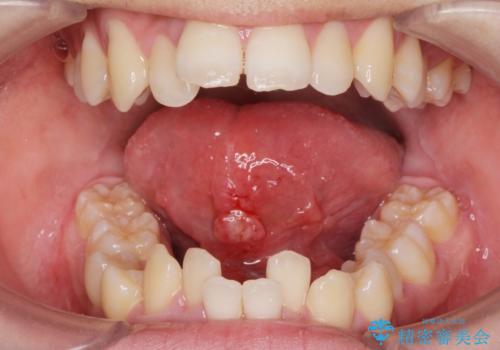

[舌小帯の形成術] 舌の動きが悪い 滑舌を改善したい!

担当医 大元洋佑